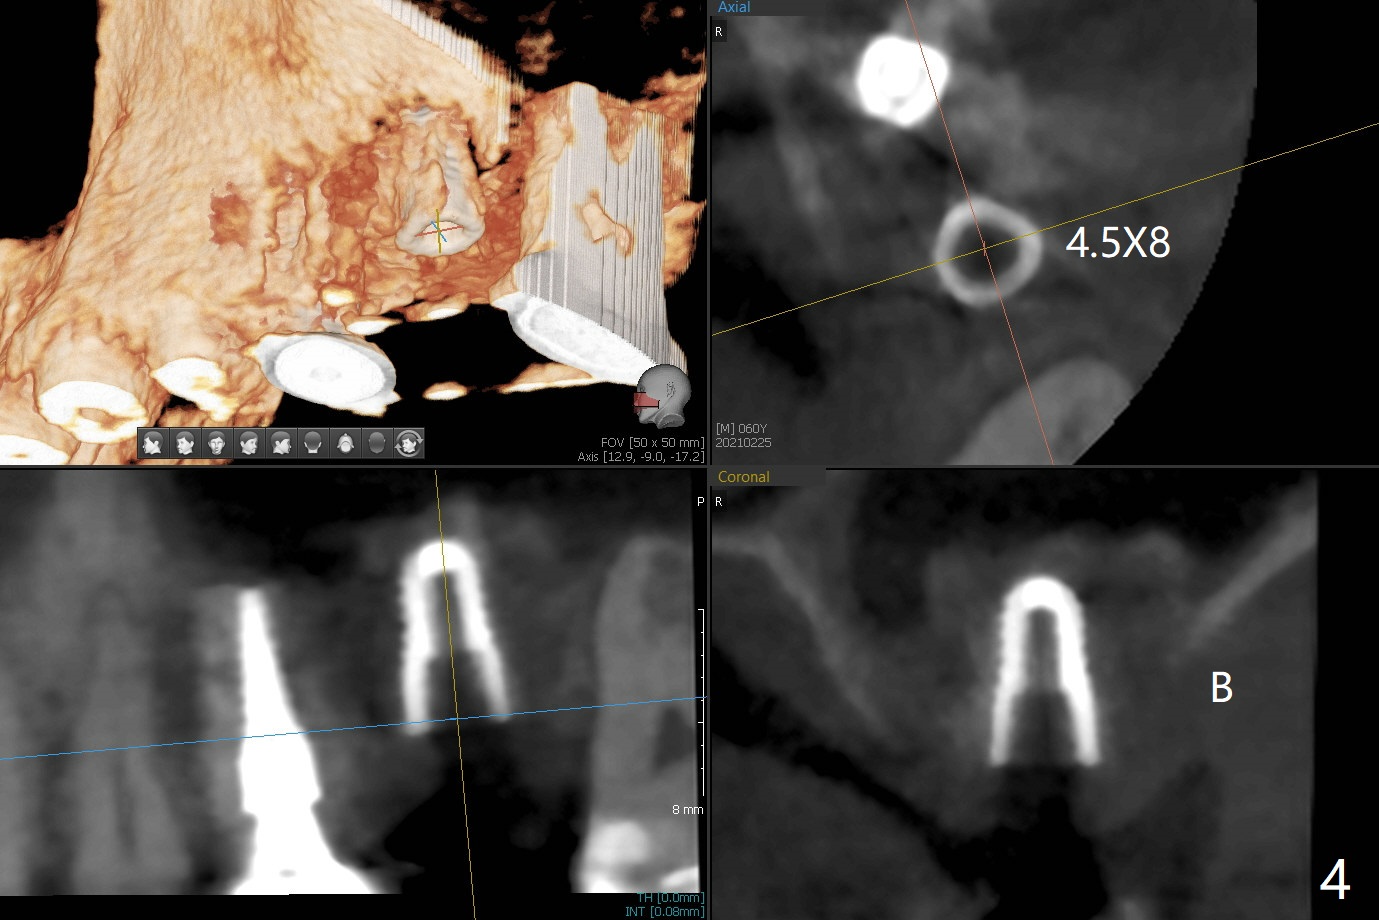

60岁男,左上6(牙根折裂严重骨质吸收)位点保存后6个月,回来植牙。术前CT显示骨质密度低,宽度足够,角化龈也宽,前后牙齿都有牙冠,制作导板麻烦,所以采纳徒手种植。使用4毫米活检打孔刀(Biopsy Punch)进入,简化手术,但是又怕开口不正,不敢用大号植体,术后CT发现钻洞偏颊侧。针对骨质密度低,使用1.2毫米钻头后(约8毫米),使用旋转式骨扩张器直至2.4/3.7毫米(图一(红虚线:原来骨质缺损)逐渐增加深度至11毫米),备洞几乎没有失去骨质,钻洞周围骨质密度谅必增高),取出最后一个扩大器后发现上颌窦底板破裂,放置粘性骨粉,使用4毫米报废植体做上颌窦提升,重复一次(图二,三),稳定性尚可。再次放置骨粉和PRF膜,使用正式植体提升(4.5x8毫米),临床上很难判断是否植体植入牙槽嵴之下(可能骨质疏松),只好拍摄CT(图四,五),好像正好牙槽嵴下,不过又植入骨粉一些(图七:*)。植体扭力~15Ncm,保险起见,放置愈合帽,表面放置少许骨粉以及打孔留下的牙龈(图六:G,之前一直泡在PRF上清液里),牙周胶水固定游离牙龈以及牙周敷料保护。术后6小时没有鼻出血。所以骨质缺损严重,植骨后,虽然缺损外形得到恢复,但是骨头质量,固定植体能力还不够。植牙时,需要适当改变手段,例如使用骨凿,提高骨质密度,而不是单纯使用钻头。术后病人恢复正常,没有疼痛,六天复诊,牙周敷料已经脱落,打孔的牙龈附着颊侧,部分骨粉暴露,但是看样子挺稳定,好像游离牙龈必须缝合。使用树脂敷料牢靠些。术后五周,伤口基本愈合,一处未愈合,与下面骨粉相通,用牙周探针稍微搅动,出血(图九)。擦干血迹,伤口还不错(图十)。术后2个月伤口好像正常愈合(图十一)。术后4.5个月根尖片显示6种植比5深,往后螺纹暴露可能性减少(图十二)。